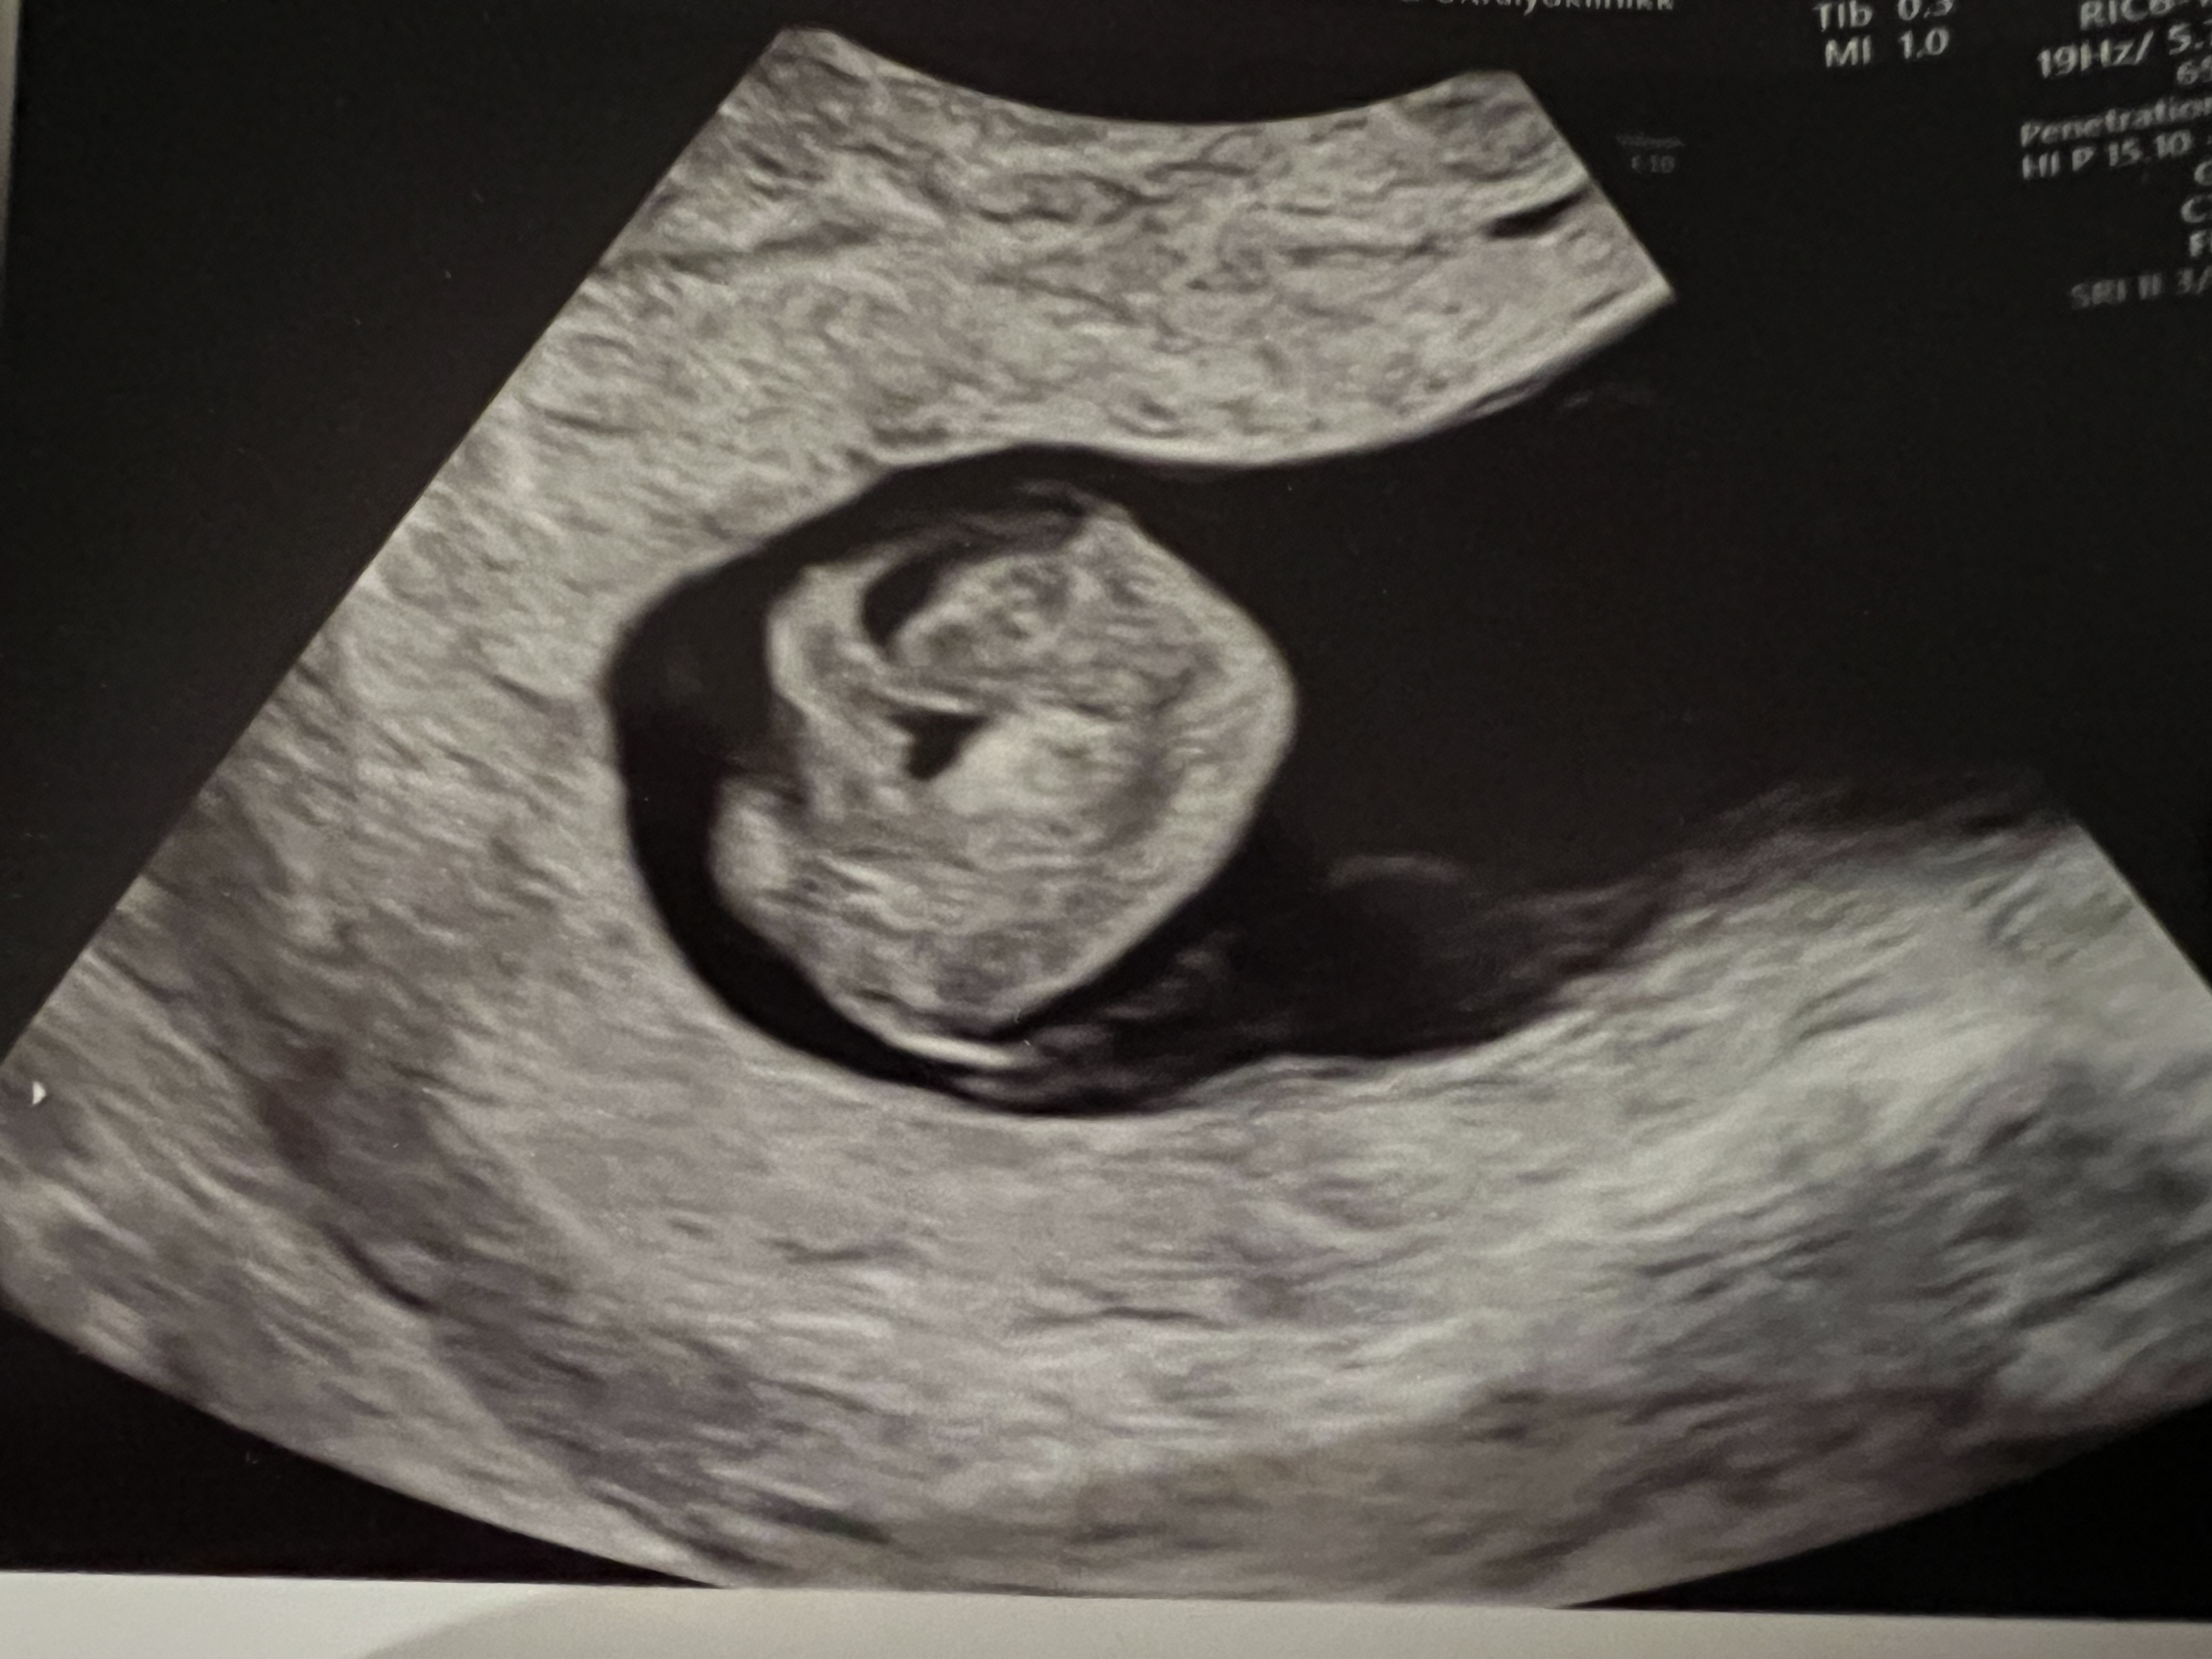

Er så betryggende å ha sett det med egne øyne og høre de magiske hjerteslagene

I følge menstermin er jeg da 13+4, i følge el er jeg 14+1 og i følge forrige ul er jeg da 14+4! Syntes jeg fikk time veldig sent, mtp at man skal få time mellom 11+0-13+6. Menstermin er jo helt feil også, siden jeg hadde el på cd 11..